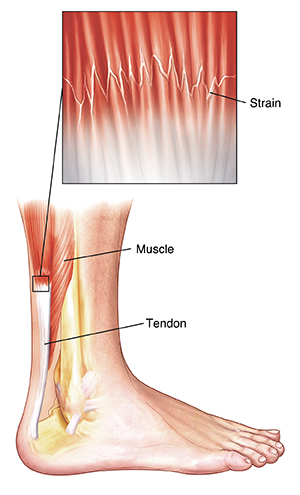

What is a strain?

A strain is an injury to a muscle or to a tendon (tissue that connects muscle to bone). It is sometimes called a “pulled muscle.” A strain happens when a muscle or tendon is stretched too far or is partially torn. Symptoms of a strain are pain, swelling, and having a problem moving or using the injured area. The hamstring (thigh muscle), calf muscle, and Achilles tendon are commonly strained.

|

| A strain is damage to a muscle or tendon. |